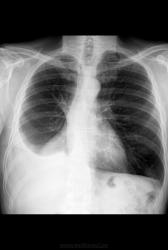

Мужчина, 56 лет. Состояние после нижней билобэктомии правого легкого по поводу центрального рака

1. В плевральной полости, безусловно, жидкость.

2. Упомянутое паракардиальное затенение имеет свое отображение и на боковом снимке

3. Учитывая объем операции (билобэктомия), эта штука вполне может быть внутриплевральным образованием (ограниченное скопление жидкости или что-то в этом роде).

Операция была проведена в другом ЛПУ и располагаем мы, к сожалению, лишь выписным эпикризом. В сравнении с описательной картиной послеоперационных снимков, количество жидкости стало меньше (уровень жидкости был на уровне переднего отрезка 4 ребра).

больному была выполнена компьютерная томография органов грудной клетки. из разговора с доктором, выполнявшим исследование, - затемнения справа представляли собой совокупность свободной и осумкованной жидкости и плевральных наслоений. В пользу благоприятного прогноза говорит еще то, что больной на данный момент набрал в весе 5 кг и в целом самочувствие стало лучше.